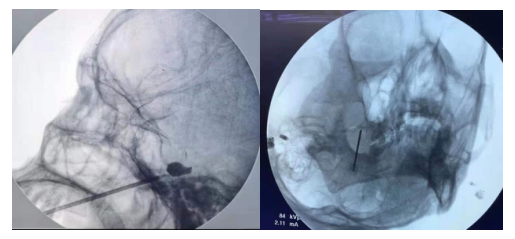

二、影像引導下脈沖射頻技術治療慢性神經性疼痛、手術后疼痛綜合癥、神經卡壓綜合癥等。

三、椎間盤微創介入技術,如:等離子消融、射頻熱凝術、臭氧髓核溶解術治療頸腰椎間盤突出癥、椎間盤盤源性疼痛。

四、經皮微球囊壓迫技術與三叉神經半月節射頻熱凝術治療三叉神經痛。

五、脊柱椎間孔鏡技術治療腰椎間盤突出癥。